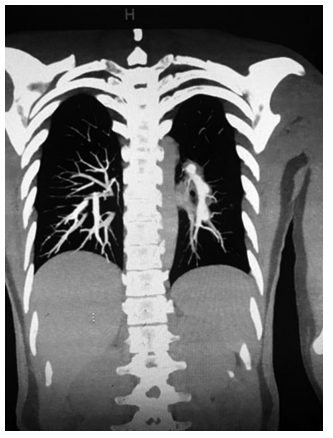

A 42-year-old female patient was admitted to the hospital with 38.6°C fever. Amoxicillin + clavulanate was prescribed due to a possible upper respiratory tract infection. Despite antibiotherapy, febrile period continued. Posteroanterior lung radiograph was performed which revealed no pathology, and the antibiotic was switched to clarithromycin. However, patient's fever persisted. When she applied to the infectious diseases outpatient clinic with 39°C of fever, acute phase reactants (APRs) were high (C-reactive protein: 56 mg/ dL). Urine culture was sterile, and there was no abnormality in lumbar puncture. Due to persistent non-productive cough, she was prescribed moxifloxacin 400 mg/day once daily. Although the patient used different antibiotics within the past three weeks, her fever continued and APRs were still high. Therefore, she was hospitalized. Aerobic/anaerobic blood cultures were sterile. Epstein-Barr virus, cytomegalovirus, and human immunodeficiency virus serologies were all negative. Abdominopelvic ultrasound was also negative for intra-abdominal abscess, hepatosplenomegaly, and pelvic pathologies. Transesophageal echocardiography revealed no abnormal findings. No tuberculous bacilli were detected by acid-resistant bacilli stain in the sputum and the urine. Gruber-Widal agglutination and Rose Bengal tests were negative. Carbapenem and antifungal drugs were added to the treatment in the second week of hospitalization. Despite these antibiotics and antifungals, her fever persisted up to 39°C. The patient had oral aphthous lesions for 10 to 12 times per year. During follow-up, thrombophlebitis developed in the vascular access in the left antecubital region. Intravenous catheter was revised, thrombophlebitis recurred on the right and confirmed by ultrasonography. After careful examination of perineum, there was a genital scar on the left labium majus. The patient was diagnosed with BS. As the fever is not a common problem in BS, PET-CT was performed to exclude possible malignancies. Moderately increased fluorodeoxyglucose (FDG) uptake (SUVmax: 1.14) was observed in the upper lobe posterior and lower lobe superior (Figure 1). Subsequently, methylprednisolone 40 mg/day was initiated. After five days of medium-dose steroid therapy, the patient’s APRs started to decrease, thrombophlebitis was cured, and her fever reached normal levels. Based on the PET-CT findings, the patient underwent pulmonary CT angiography and three aneurysmatic dilatations with a diameter of 11 mm were observed in the left main pulmonary artery (Figure 2). In the light of these findings, the patient was given methylprednisolone 1,000 mg for three days. Cyclophosphamide 1,000 mg/month was also planned with six cycles. After cyclophosphamide treatment, the patient received low-dose steroid and azathioprine 2 mg/kg/day and did not experience any fever attacks after approximately nine months of follow-up. No increase in the aneurysm size was detected in CT angiography at one year. A written informed consent was obtained from the patient for all diagnostic and therapeutic procedures.